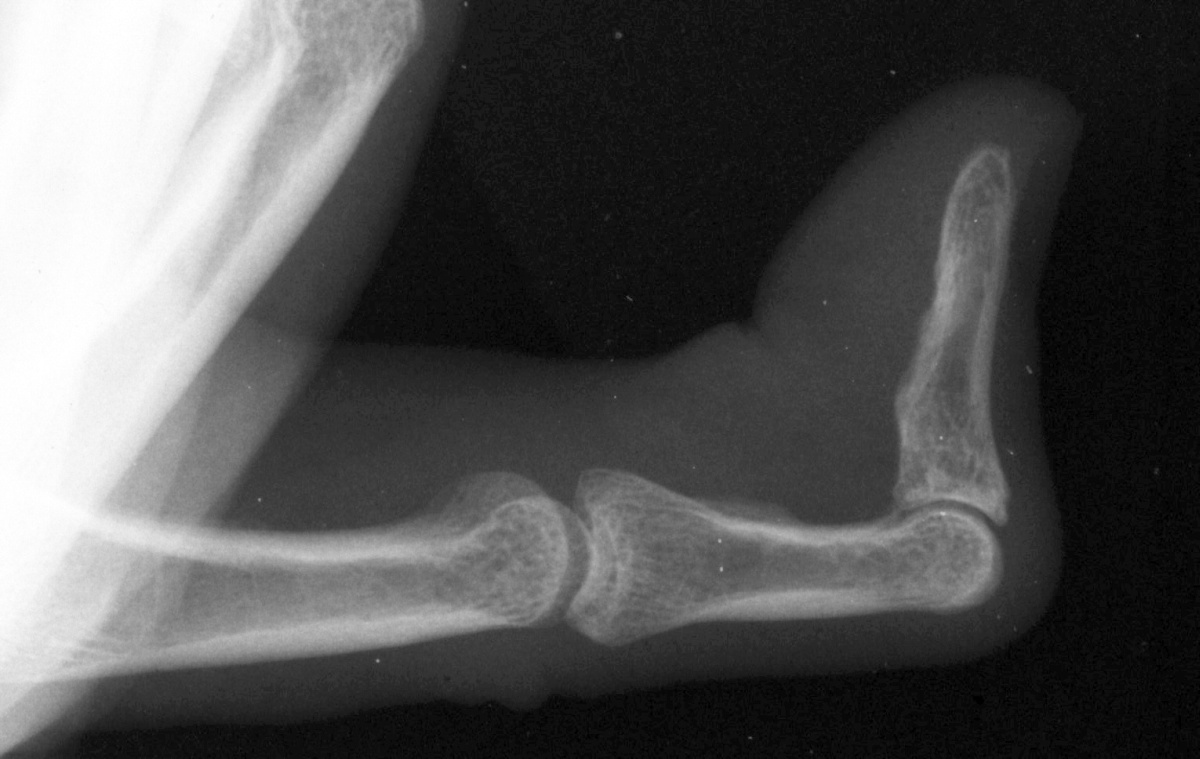

Case 4.

57 year old right handed man with a 22 year

history of Dupuytren disease affecting his

left small finger.

Radiograph of affected finger, 90° contracture.